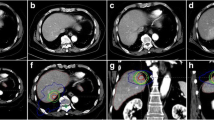

Quantitative assessment of the lipiodol/diaphragm position

Of 29 (55 %) lipiodolized tumors, 16 showed contrast that qualified for the purpose of target localization on the 4D-CBCT and were entered in the subsequent analysis that included 87 4D-CBCT scans. The relationship between the absolute lipiodol and diaphragm centroid positions (Fig. 1) showed statistical significance in all directions, with Pearson’s correlation coefficients (r) of 0.80 (LR), 0.78 (SI), and 0.83 (AP). The quantitative assessment of the lipiodol/diaphragm-based treatment setup and the tumor prediction error using lipiodol as the reference are listed in Tab. 1. The group means did not significantly differ between the absolute lipiodol and diaphragm positions for all directions, and insignificantly differ from 0 except for the CC direction where both lipiodol and diaphragm positioning showed an average offset of the estimated position towards the caudal direction with respect to the planning MidV position.

In our study, almost all patients showed decreased lipiodol contrast on the 4D-CBCT as compared to on the 4D-CT, and about half of the lipiodolized tumors were abandoned for clinical setup because the lipiodol contrast was too low. The clinical implication of changing from lipiodol-guided to diaphragm-guided setup due to the absence of lipiodol contrast on 4D-CBCT without adapting the PTV margin may warrant further investigation. According to our initial experience, the visibility of the lipiodol deposit on the 4D-CBCT critically depended on its initial pattern on the planning CT, and that lipiodol deposits that showed higher Housfield Unit (HU) on the 4D-CT usually had better visualization on the 4D-CBCT than those with lower HU. For our clinical protocol, the lipiodol amount was limited to 20 ml to avoid liver failure. It was known that higher dose of lipiodol is needed for large and hypervascular HCC to attain complete filling of the tumor vessel bed. As reported in Chen et al. [16], lipiodol retention showing homogeneous and defective patterns was more frequent in the patient group receiving the high dose (20–53 ml) than that given the low dose (5–15 ml). Based on the initial findings of this study and previous reports, we have started to adjust the lipiodol volume to achieve better lipiodol contrast on 4D-CBCT for tumor localization.